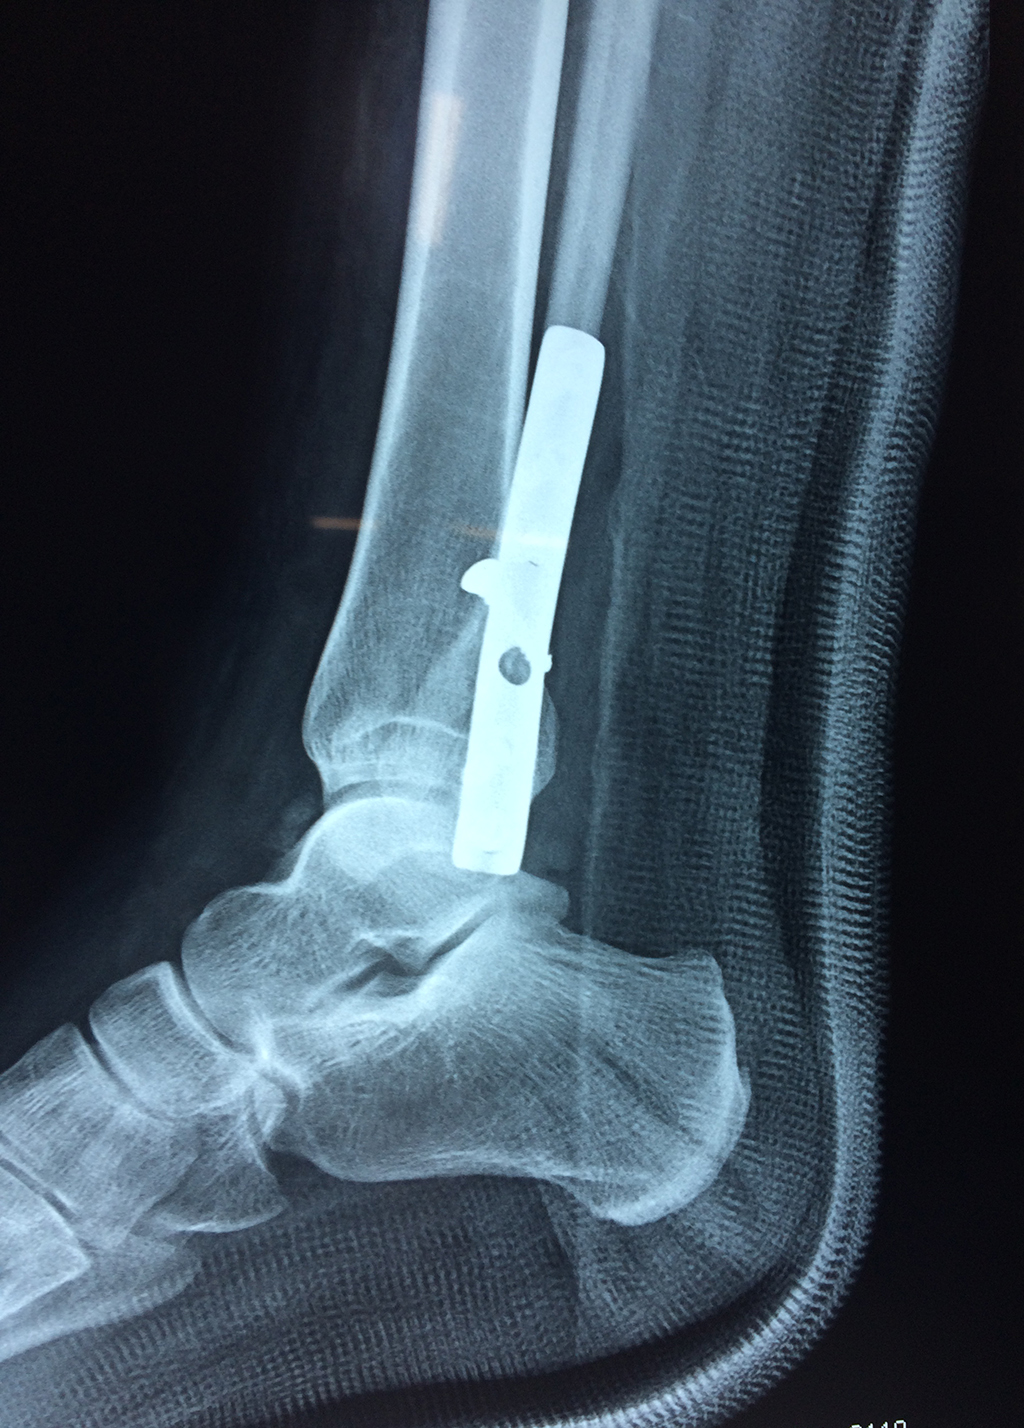

Cuando se necesita cirugía, es probable que esta implique el uso de clavijas de metal, tornillos o placas para sostener los huesos en su lugar mientras la fractura se consolida. Los elementos de soporte pueden ser temporales o permanentes.